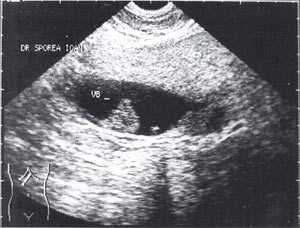

Кроме типичного вида, "желчный сладж" может иметь особый вид, похожий на круглое полипоидное объемное образование с острыми краями или неравномерным контуром ("опухолеподобный желчный сладж" или "сладжевые шарики" [12, 13]). При изменении положения больного видны перекатывающиеся или разрушающиеся шарики сладжа, затем снова формирующие исходное объемное образование (рис. 2-8).

Рис. 7. "Желчный сладж" в виде шара.

Рис. 8. Шароподобный "желчный сладж".